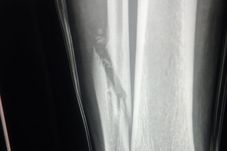

Prima dată s-a accidentat când evolua la Lech Poznan. A doua oară la naţionala Bosniei, imediat după ce fusese introdus pe teren. A treia oară şi a patra oară în tricoul Craiovei, într-un meci la Voluntari şi acum, atacat criminal de Mihalache. Cele 4 accidentări grave ale lui Elvir Koljic în decurs de 3 ani. Unul dintre cei mai ghinionişti jucători din lume. Bosniacul are fractură de peroneu şi va rata tot acest sezon.